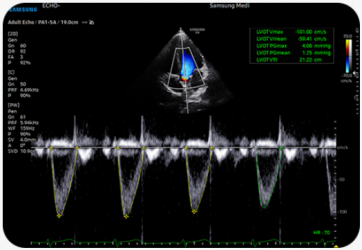

Automatizovaný nástroj pro tvorbu reportů diagnostiky srdce |

Funkce HeartAssist&trade, založená na technologii Deep Learning, zajišťuje automatickou klasifikaci ultrazvukového obrazu na zobrazení potřebná pro diagnostiku srdce a automaticky poskytuje výsledky měření.

Měření ejekční frakce levé komory |

AutoEF je funkce, která pohodlně měří a kvantifikuje ejekční frakci. Výběrem tří bodů levé komory se vypočítá objem na konci systoly a na konci diastoly, což napomáhá rychlému a efektivnímu posouzení funkce srdce.